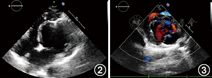

入院后生化检查:总胆固醇3.4 mmol/L,低密度脂蛋白胆固醇1.9 mmol/L;甲状腺功能三项无异常;空腹血糖4.4 mmol/L;急查心肌酶无异常,肌钙蛋白I阴性;血尿常规、肝功能、肾功能和凝血功能正常。器械检查:(1)X线胸片:心影不大,呈球形,心胸比例0.44。(2)12导联心电图(图1):窦性心律,电轴右偏,胸前导联R波递增不良,V1或V2导联正向T波高度大于V5或V6导联。(3)超声心动图(图2、图3):左心室增大,呈球形改变,左心室横径59 mm,纵径84 mm,前后径64 mm;左心室射血分数52%,短轴缩短率26%;左心室心尖部扁平,似被截短;左心室室间隔均凸向右心室,前间隔、后间隔中间段至心尖段心肌变薄(厚度4.8 mm),回声增强,运动消失;前间隔、后间隔基底段心肌厚度正常,运动减弱,呈瘤样凸向右心室,致右心室流出道局部梗阻(内径变窄,8.5 mm;流速偏快,1.95 m/s;右心室流出道压差20 mmHg);左心室乳头肌均附着于扁平的左心室前壁心尖部;舒张早期二尖瓣血流峰值速度(E)1.07 m/s、舒张晚期二尖瓣血流峰值速度(A)0.76 m/s,E/A=1.4;其余房室腔内径正常;右心室射血分数58%。(4)动态心电图:窦性心律,电轴右偏,胸前导联R波递增不良,Tv1(Tv2)>Tv5(Tv6);24 h最低心率54次/min,最高心率121次/min,平均心率72次/min;偶发房性早搏;无室性心律失常;心率变异性正常。(5)冠状动脉造影未见明显异常。(6)左心室造影:心腔扩大,左心室心尖部在舒张期呈球样扩张,且搏动减弱。(7)心脏磁共振(图4):左心室舒张期呈球形扩张,舒张末期前后径64 mm;室间隔向右心室面突出;心尖及心尖段室间隔左心室面可见脂肪替代且运动减低,中间段室间隔变薄(厚度5 mm);右心室心尖向左延伸,包绕发育不良的左心室心尖部;左心室前后两组乳头肌均附着于前壁心尖部。

LVAH有特殊的形态学改变,影像学诊断标准包括:(1)最突出特征是左心室心尖部扁平,乳头肌附着点以远似被截平;(2)室间隔凸向右心室侧,致使左心室横径增加,纵径相对缩短,失去其圆锥形外观而呈球形;(3)左心室乳头肌附着于其扁平的前壁心尖部,而非前侧壁和后中壁,此种改变可致不同程度的二尖瓣反流;(4)右心室形态学改变表现为远端延长,并包绕发育不良的左心室心尖部,呈香蕉状,功能多正常;(5)大部分患者左心室心尖部可见脂肪替代[2]。超声心动图是临床筛选LVAH的最常用方法,但易受操作者经验及声窗的影响。心脏磁共振是目前诊断LVAH的最好方法,有良好的软组织分辨率,本例患者最终经心脏磁共振确诊。